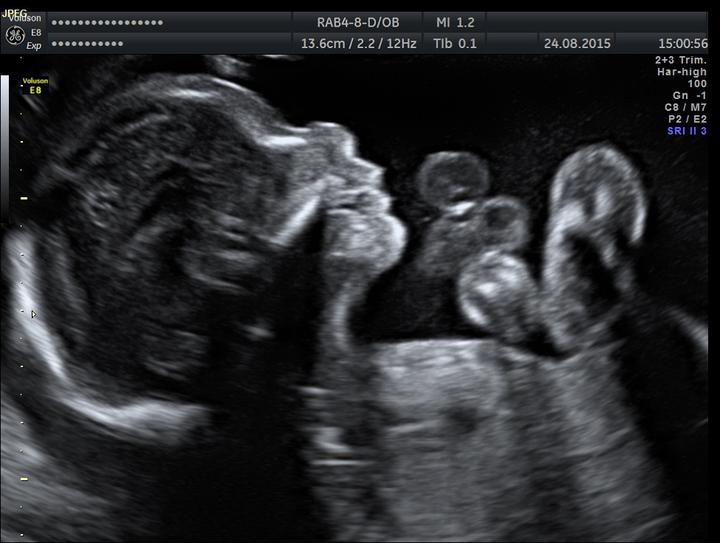

Dnešní UZ 30+4 tt dopadl na jedničku, vše v pořádku, váha 1550. 😃 Je zatím zadečkem dolů, tak snad se brzy otočí..